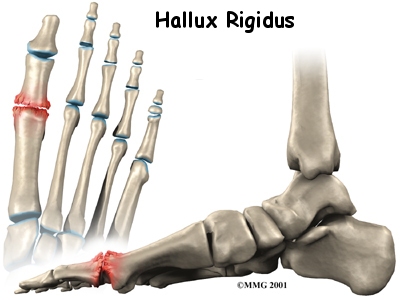

Hallux Rigidus

Hallux rigidus is a degenerative type of arthritis that affects the large joint at the base of the big toe (sometimes called the great toe). Degenerative arthritis results from wear and tear on the joint surface over time. The condition may follow an injury to the joint or, in some cases, may arise without a well-defined injury.This guide will help you understand: